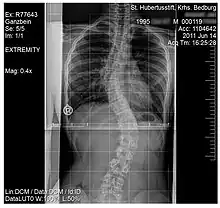

Scoliosis

An ex-ray of a spine affected by scoliosis belonging to a 15 year old

Scoliosis, is a medical condition where a person's spine has several irregular curves that are located between the neck and the pelvis.[8] Symptoms of scoliosis in mild cases usually exhibit abnormal posture, back pain, tingling or numbness in the legs and in worse cases can exhibit breathing problems, fatigue, permanent deformities and in rare cases heart problems.[8]